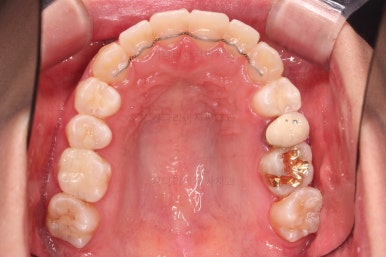

악궁확장을 먼저 시행합니다.

아랫니에 비해서 윗니의 악궁의 폭이 좁기 때문에 가로폭을 먼저 개선합니다.

악궁확장 이후, 유지단계 동안 확장의 유지에 필요한 치아를 제외하고는 브라켓을 부착하게 됩니다.

이번 환자분이 선택한 장치는 엠파워 클리어라고 하는 자가결찰 세라믹 장치인데요.